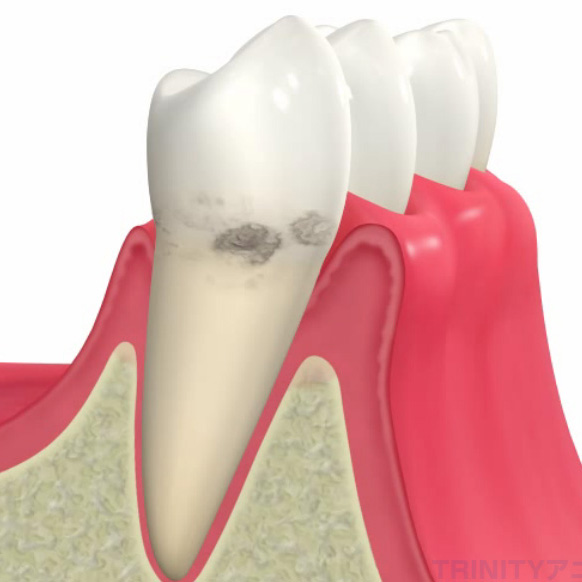

⼝の中にたまった⻭垢(プラーク)が原因で、⻭⾁(⻭茎)の炎症から始まり、

やがては⻭を⽀える⾻を溶かして⻭を失ってしまう病気です。

⻭周病は⻭を⽀え⾻を溶かす病気です。レントゲンを⽤いて、⻭を⽀える⾻がどのくらい⻭周病により溶かされているかを確認し、重点的に治療が必要な場所などを特定します。

⻭周病の進⾏度合いの指標となる、「⻭周ポケットの深さ」、「出⾎がある部位」、「プラークの、付着度合い」、「⻭の動揺度合い」などを検査し、どのような⻭周病治療が最適かを精査します。この数値を定期的にチェックすることにより、⽣涯、⻭周病のない⼝腔状況への維持管理を⾏います。